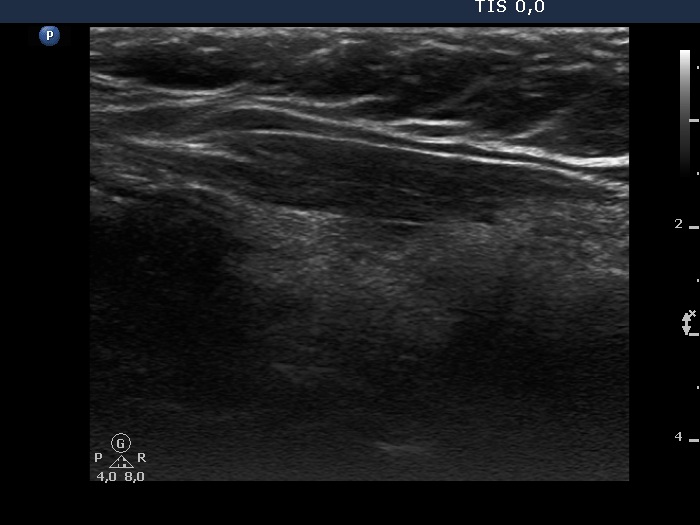

Consecutive patients with the final diagnosis of Hashimoto's thyroiditis - case 6 (254) (ultrasonographic picture 2)

Right lobe, longitudinal scan.